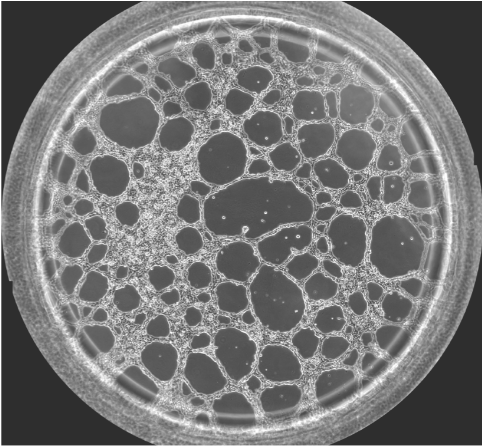

圖一 血管生成鏡檢圖

無(wú)論原發(fā)性腫瘤還是繼發(fā)性腫瘤,一旦生長(zhǎng)直徑超過(guò)1~2 mm,都會(huì)有血管生成。這是由于腫瘤細(xì)胞自身可分泌多種生長(zhǎng)因子,誘導(dǎo)血管生成。多數(shù)惡性腫瘤的血管生成密集且生長(zhǎng)迅速。因此,血管生成在腫瘤的發(fā)展轉(zhuǎn)移過(guò)程中起到重要作用,抑制這一過(guò)程將能明顯阻止腫瘤組織的發(fā)展和擴(kuò)散轉(zhuǎn)移。于是體外的血管生成實(shí)驗(yàn)就能很好的模擬腫瘤的血管發(fā)生過(guò)程,并且適合研究藥物對(duì)這一過(guò)程的影響實(shí)驗(yàn)。本實(shí)驗(yàn)以HUVEC細(xì)胞為例,介紹這一實(shí)驗(yàn)的詳細(xì)過(guò)程。